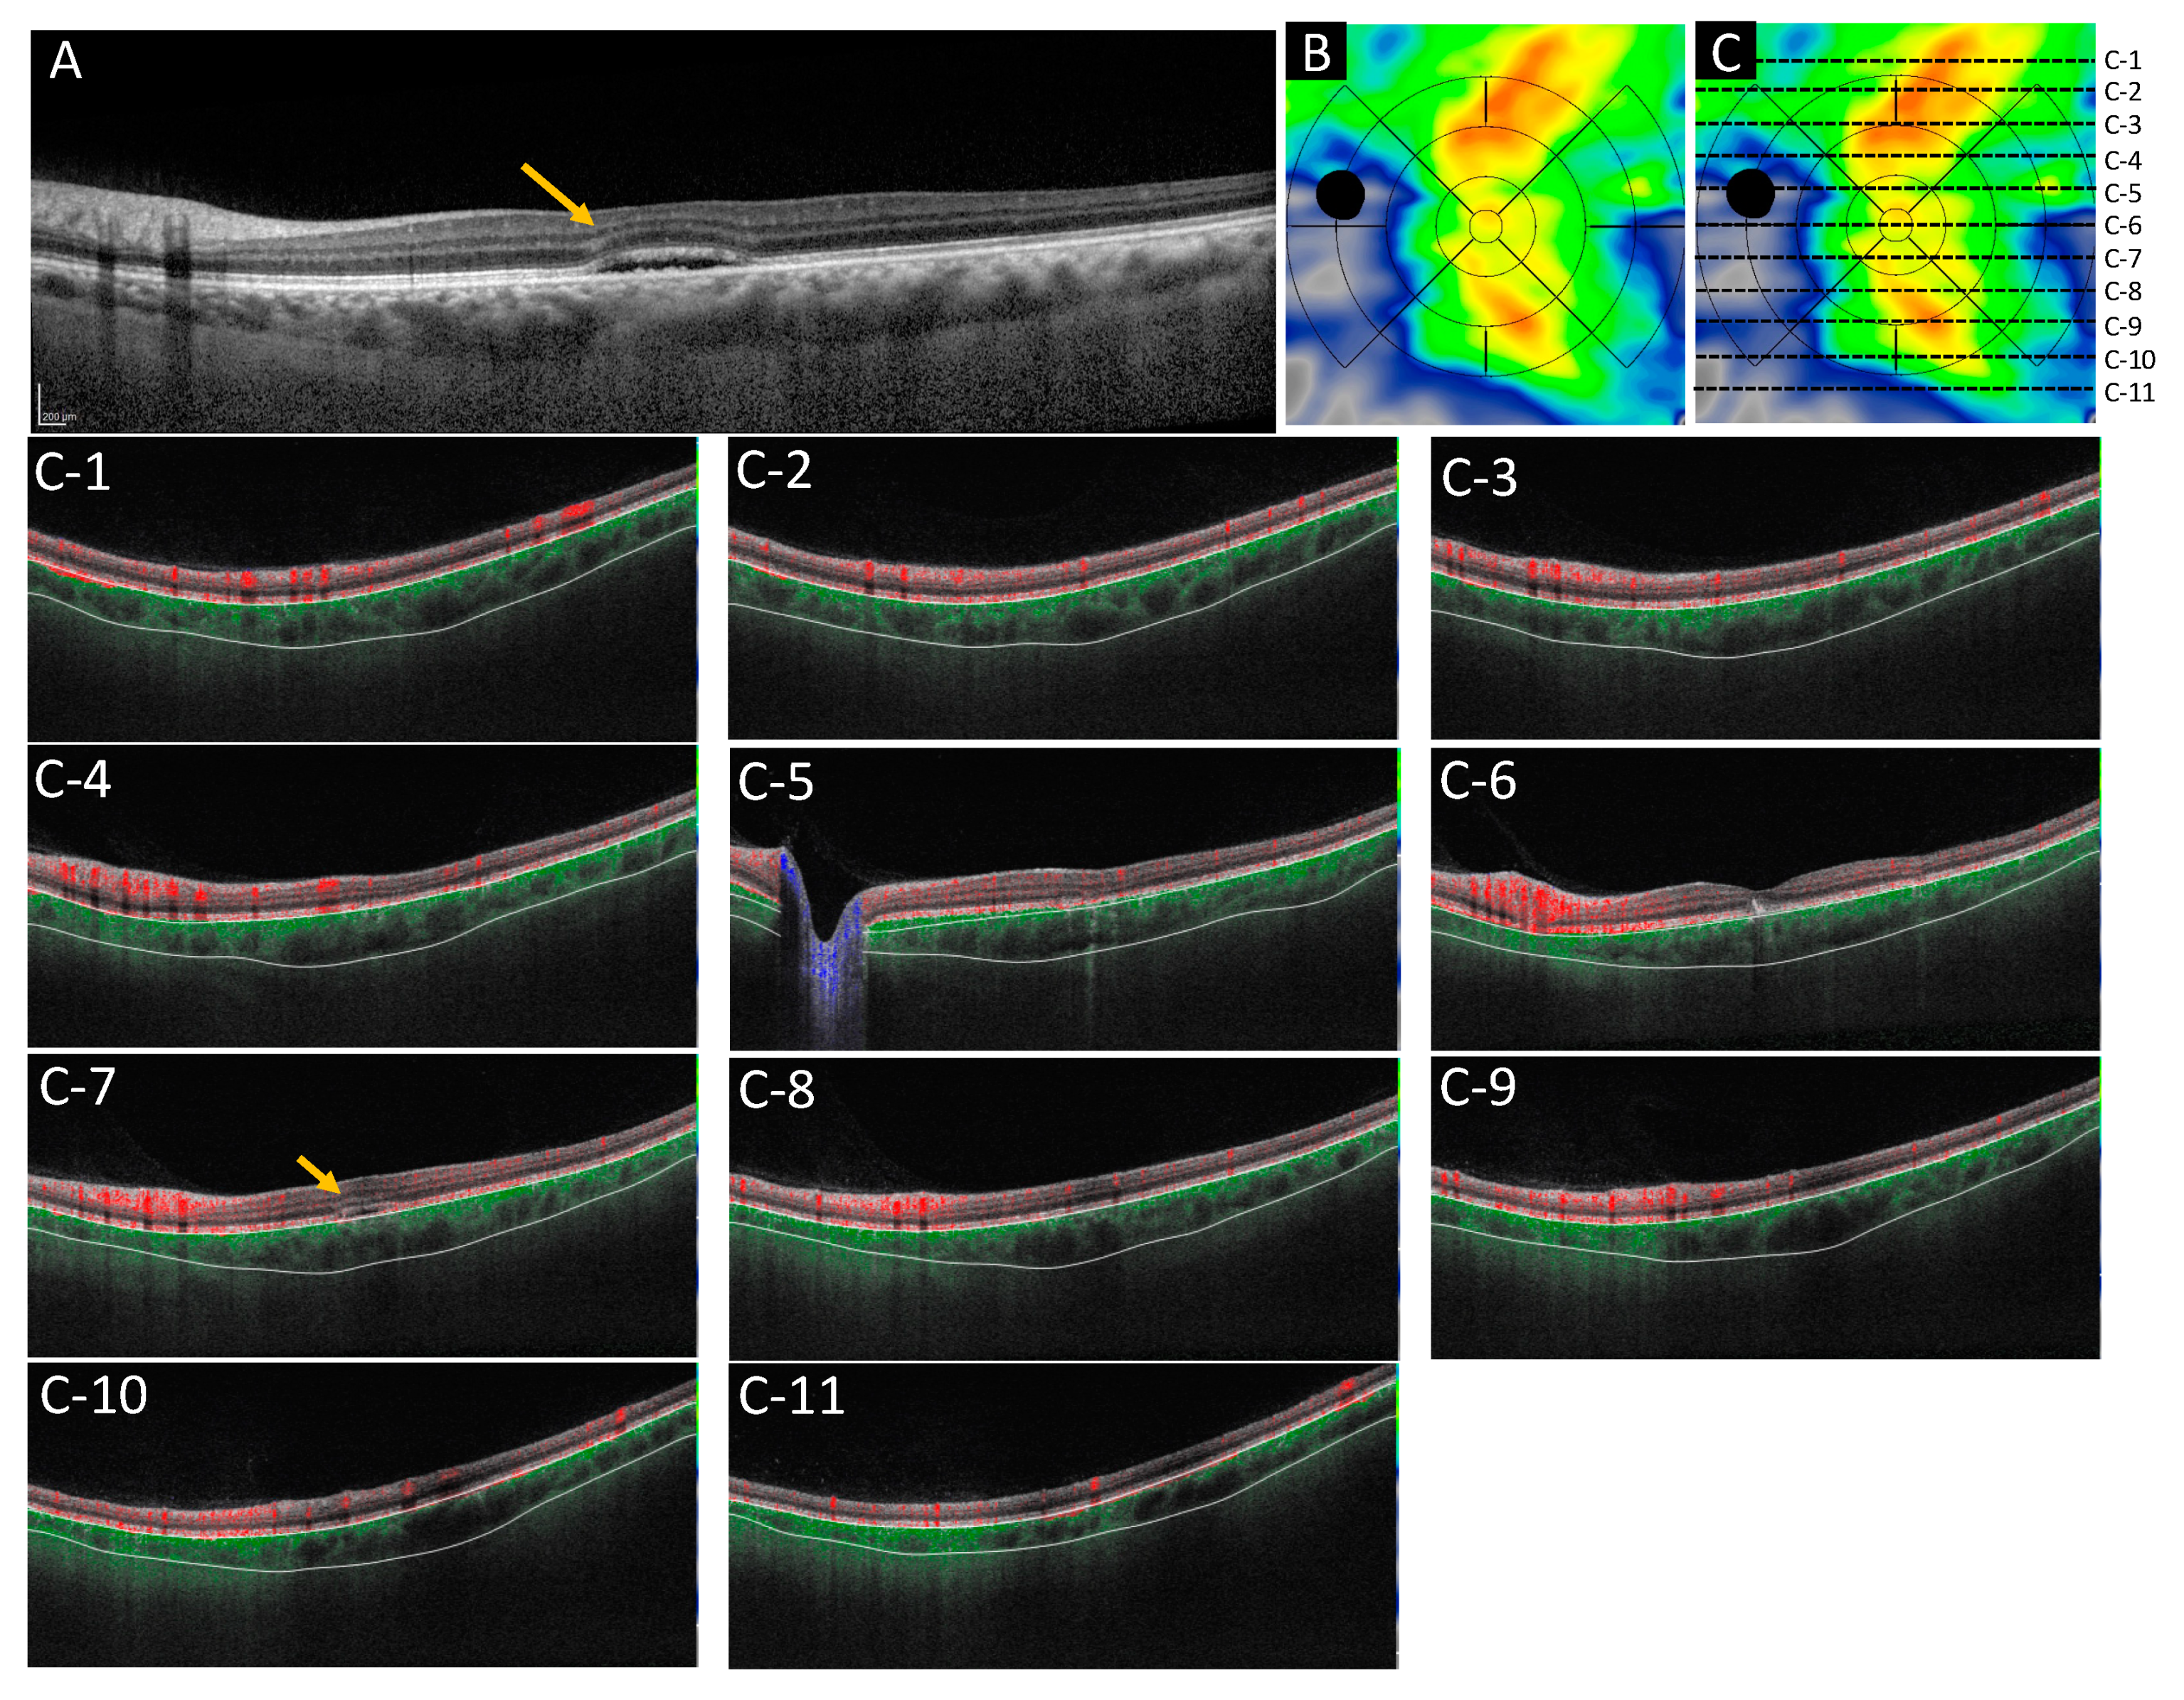

2.5. Case Presentations

2.5.1. Case 1: A 46 Year-Old-Male